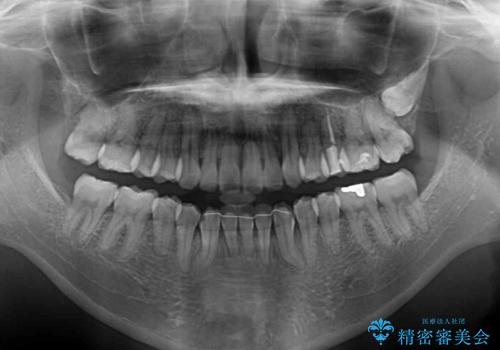

下顎前歯が1本欠損しており、上下アーチはアンバランスとなりますが、インビザラインを用いて上下の隙間を改善しながら歯列を整えることとしました。

下顎前歯の1本欠損により左右の咬合が不安定となり、治療経過で噛みにくい状態が続きましたが、最終的には違和感なく噛めるようになりました。